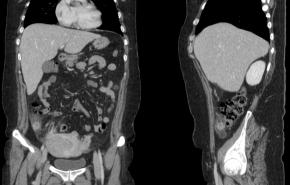

[Gastrointestinal [GI]] 40 Years/F, Right lower quadrant pain

Questions What is the most likely diagnosis?

Answer Epiploic appendagitis

Comments Epiploic appendagitis is a benign and self-limiting inflammatory condition involving an epiploic appendage. On ultrasound, it typically presents as a noncompressible, oval-shaped hyperechoic mass adjacent to the colon, often surrounded by a hypoechoic rim that reflects inflammation of the visceral peritoneum. Color Doppler imaging usually demonstrates absent or minimal internal vascularity within the lesion. The adjacent bowel wall is generally normal or only mildly reactive, which helps differentiate epiploic appendagitis from acute appendicitis or diverticulitis. Laboratory inflammatory markers are often normal or only mildly elevated. Accurate recognition of these characteristic ultrasound findings can obviate unnecessary surgical intervention, as conservative management is usually sufficient. Awareness of this entity is particularly important in the evaluation of patients presenting with acute abdominal pain.

Keywords Right lower quadrant pain; Epiploic appendagitis